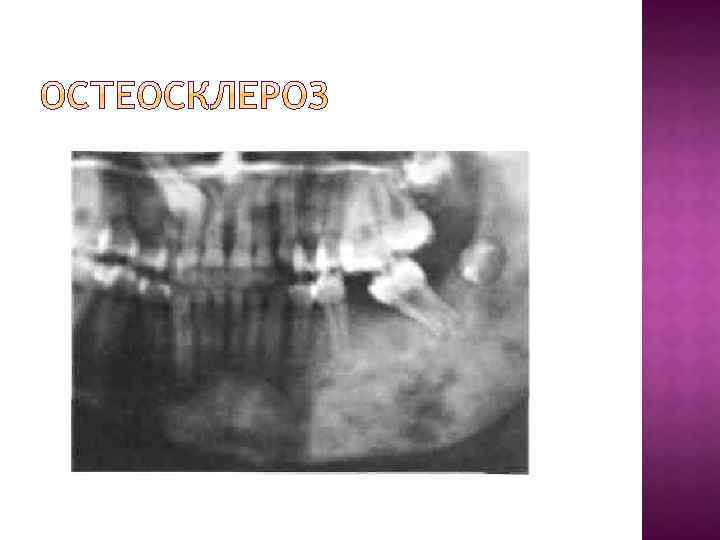

При заболеваниях пародонта наиболее часто выявляются следующие патологические изменения в костной ткани. Остеопороз - дистрофический процесс в костной ткани, рентгенологически проявляющийся ее повышенной прозрачностью, с уменьшением количества костной ткани на единицу площади без изменения размеров кости. Деструкция - разрушение кости и замещение ее патологической тканью (грануляциями, гноем, опухолью); на рентгенограмме очаг деструкции представлен в виде участка просветления с нечеткими, неровными контурами. Атрофия - уменьшение объема всей кости или ее части вместе с убылью костной ткани. Остеосклероз - процесс противоположный остеопорозу, увеличение количества костной ткани на единицу площади без изменения размеров кости, рентгенологически проявляющийся снижением прозрачности костной ткани.